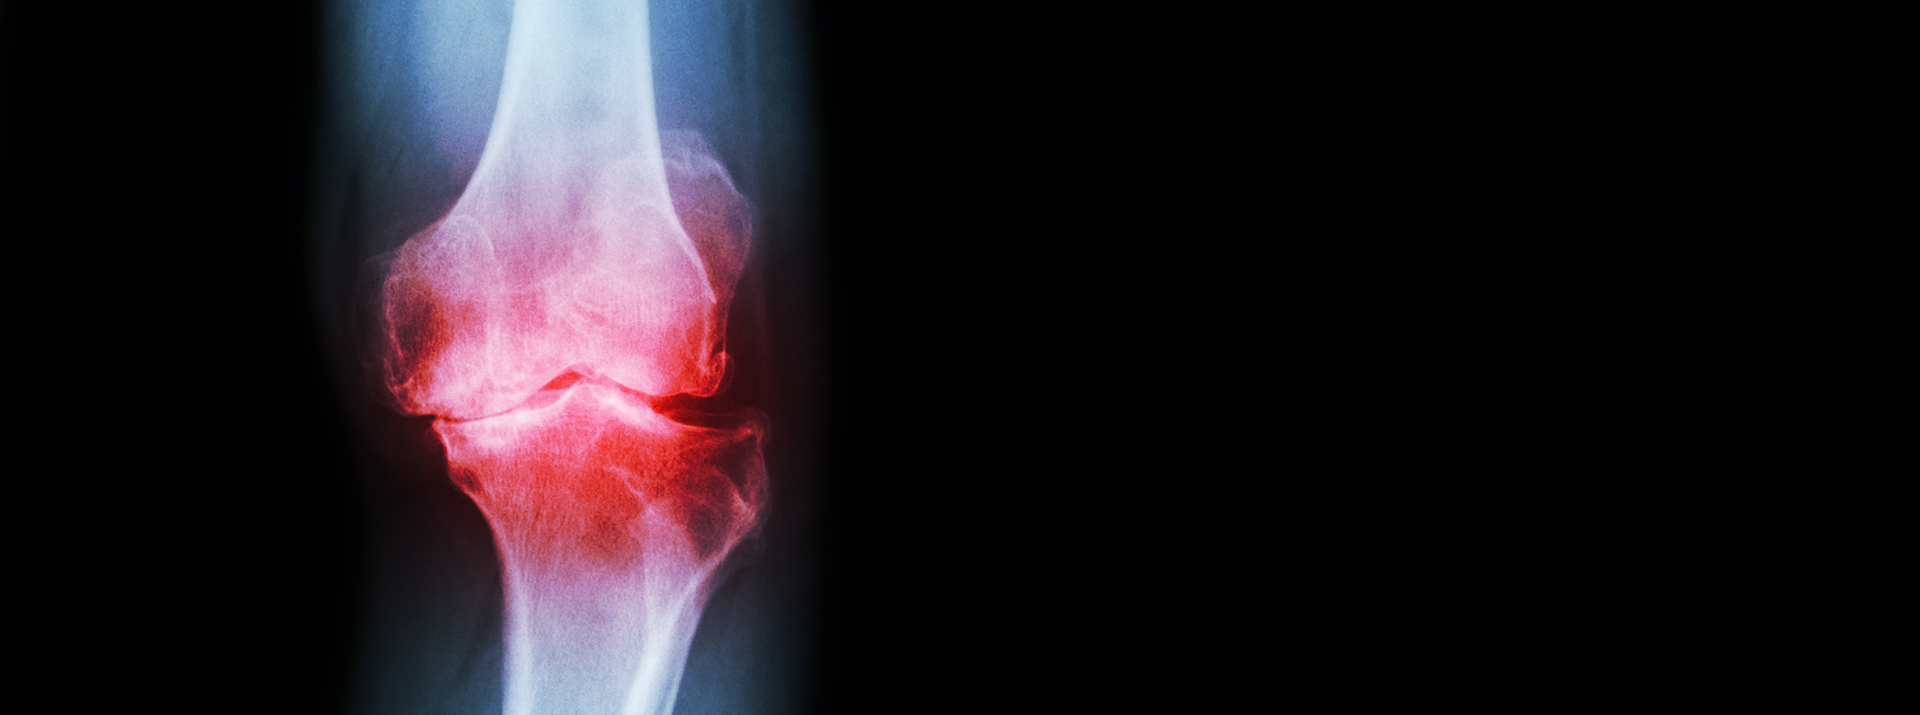

osteoarthrite

¿Cómo tratar la osteoartritis de la rodilla con la terapia de ondas de choque?

La rodilla es una de las articulaciones más afectadas por los cambios artríticos. La probabilidad de desarrollar artrosis de rodilla a lo largo de la vida es, en promedio, del 45%.  Para aliviar el dolor de los pacientes enfermos, retrasar las intervenciones quirúrgicas o, en el mejor de los casos, evitarlas por completo, se deben tomar medidas a tiempo.